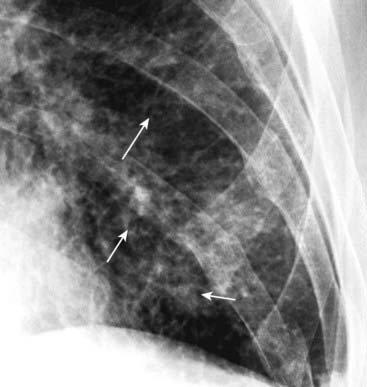

imageAlso, in a child the thymus gland may overlap portions of the heart and sometimes mimic cardiomegaly. The normal thymus may be seen on conventional chest radiographs up to 3 years of age and sometimes may be seen as late as 8 years of age. The normal thymus gland has a somewhat lobulated appearance, especially where the ribs indent it (Fig. 9-5).

Figure 9-5 Normal thymus gland.

The thymus gland may overlap the upper portion of the cardiac silhouette and can be mistaken for cardiomegaly in a child. One aid in identifying the thymus gland is that it is frequently lobulated in appearance (solid white arrows). Although the thymus gland will usually involute by age 3, it may still be normally visible in children as old as 8 years of age.